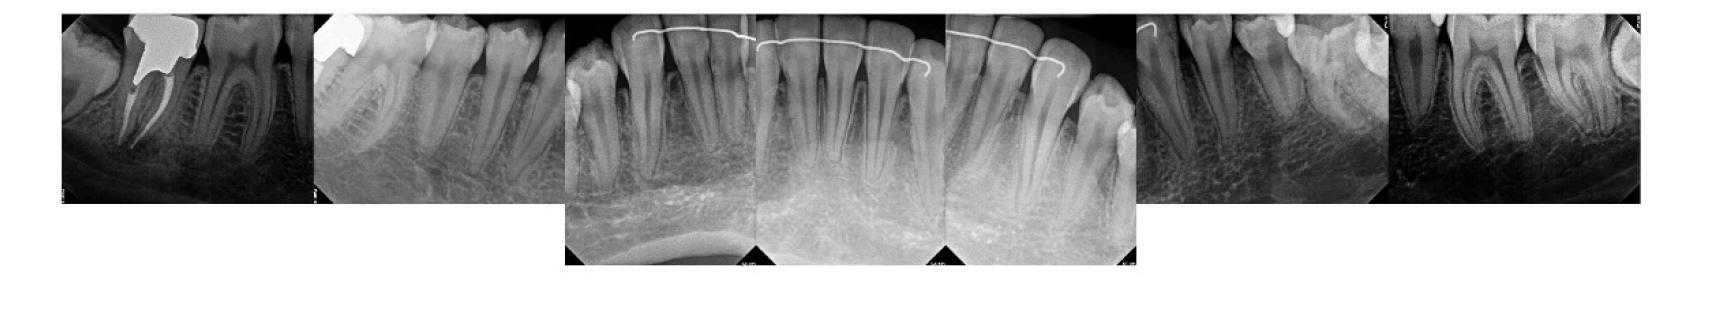

Figure 1. Example of characteristic Wickham striae and reticular pattern on buccal mucosa used to clinically diagnose OLL and OLP cases. Erythematous areas also seen. Figure 2. Frequency and percent of study patients using specific medications with color-coded drug classes.

Figure 3. Frequency of hypertension medications by specific classes.

The most common medication taken among subjects was metformin, comprising 24.6% (n=40). The most common phar macologic class was statin medications, at 36.4% (n=59); specifi cally, 15% (n=25) of patients took atorvastatin and 9% (n=15) took simvastatin. We also discovered that 17.9% (n=29) took proton-pump inhibitors and, interestingly, 16.7% (n=27) took le vothyroxine. These results are summarized in Figure 2 and Table 1.

Antihypertensives were the most common therapeutic class of medications among our subjects, at 49.4% (n = 80). As seen in Fig ures 2 and 3, when hypertension medications (color-coded green) are further subdivided into pharmacologic classes, beta blockers were the most associated with OLL/OLP, followed closely by angiotensinII-receptor blockers (ARBs) and calcium channel blockers (CCB). The thiazides are the next frequent type of hypertension medications taken by our OLL/OLP patient cohort. To our knowledge, our study is the first to further subtype the large and diverse class of hyperten sion medications associated with oral lichenoid lesions.